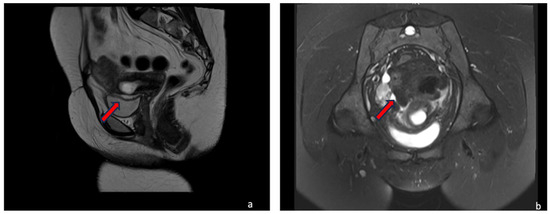

4.1.1. Case 1 (CSP Type I)

4.1.2. Case 2 (CSP Type II)

4.1.3. Case 3 (Low-Implanted Pregnancy)